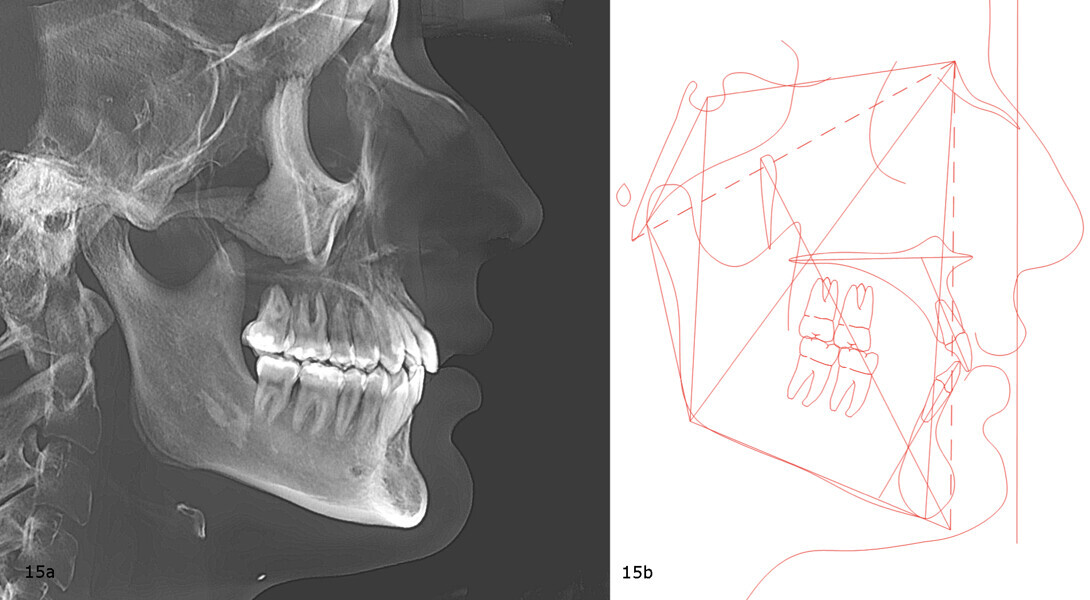

Beyond the occlusal and aesthetic improvements, vertical control had delivered significant facial changes, including a shortening of the lower facial third, improved upper and lower lip support, and an advancement of the chin by 5 mm (Fig. 13). Importantly, all of these changes were achieved without exacerbating the initial root resorption, as confirmed by the final panoramic radiograph (Fig. 14). The final cephalometric radiograph and tracing confirmed the successful treatment outcome, showing clear evidence of mandibular auto-rotation and a shortened lower facial third, contributing to improved facial proportions (Fig. 15).

The final panoramic radiograph showed good root parallelism and confirmed that all treatment objectives had been met without root resorption or harm to periodontal health (Fig. 49). The final cephalometric radiograph and tracing confirmed the mandibular auto-rotation: a facial axis of 95° pretreatment to 97° post-treatment and an anterior facial height of 117.5 mm pretreatment to 115.9 mm post-treatment (Fig. 50).